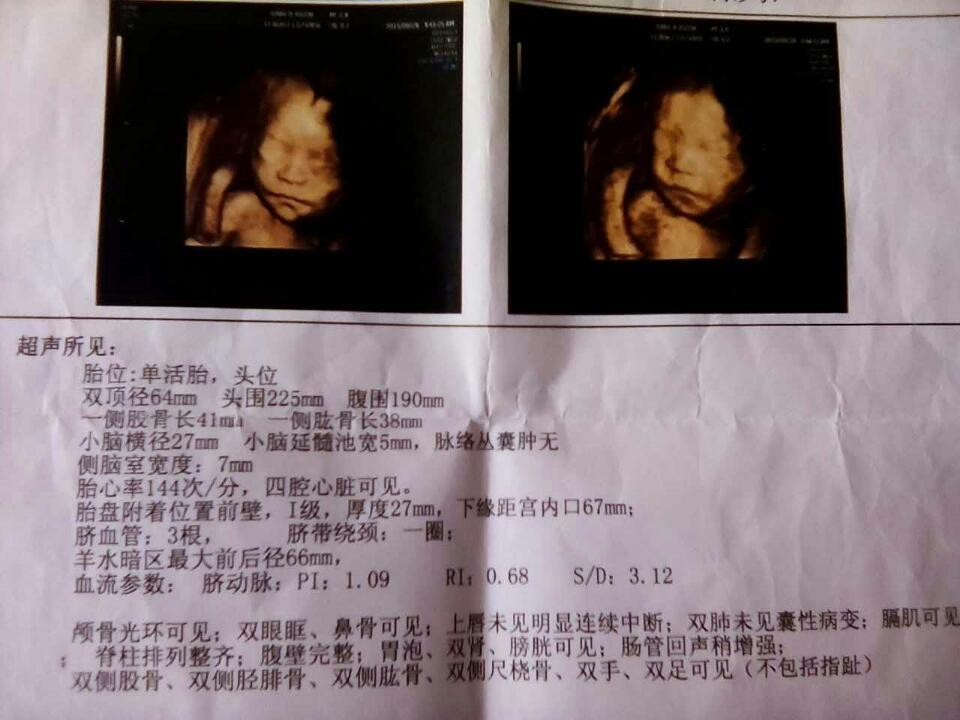

四维顺利,亲们帮我看下,男宝还是女宝呢? 四维顺利,亲们帮我看下,男宝还是女宝呢? 点击展开 小左小右_RcxF 2015-09-02 08:14 为您推荐: 其他回答 呵呵,给红包医生就知道男孩女孩了 137*****920_FVbK 2015-09-02 11:39 只要你提供数据正确结果有八成是女宝。我跟很多人算过都准的 男宝@女宝 2015-09-02 09:02 恭喜宝妈,也是女宝! 男宝@女宝 2015-09-02 09:01 看不出来。 嫻嫻 2015-09-02 08:59 看不出来! 无可救药的傲、 2015-09-02 08:56 加载更多 相关问题 做完四维啦,宝宝健康,亲们谁能帮我看看是男宝女宝啊😄 27周四维通过了!宝妈们来猜猜男宝女宝吧!猜对错都赢好运哦! 亲们,请帮我看下这份四维报告有没有什么问题 有没有说到有没有畸形什么的?